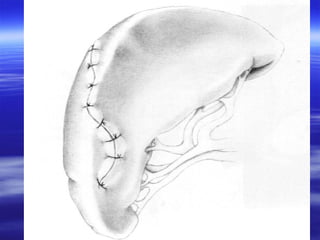

Splenorafi

 Dalak parankiminin sütürasyonunu içerir.

 Splenik kanamayı kontrol altına almak ve yaralanmayı

net bir şekilde ortaya koymak için dalak damarlarına

parmak ile basınç uygulanır

 Basit bir laserasyon varılığında ve çocuklarda direkt

sütürasyon uygulanabilir. Ancak erişkinlerde ve difüz

kanama varlığında iç içe geçen mattress sütür

uygulanır.

 Mattress sütür , yastıklanmış (pledgeted) sütürler ya

da hemostatik tampon üzerinden emilebilen

monofilaman materyeller ile de dikilebilir.